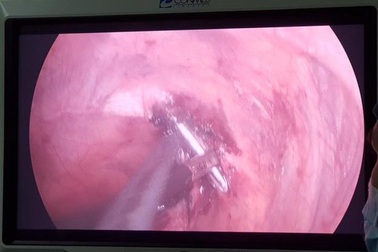

Kỳ lạ chiếc đinh "chui" xuyên qua phổi, tuỷ sống bệnh nhânCác bác sĩ BV Đa khoa Đức Giang vừa thực hiện ca can thiệp đặc biệt, rút chiếc đinh vốn có tác dụng "ghim" xương bệnh nhân sau một cuộc phẫu thuật đã bị tuột khỏi xương, chui vào tuỷ sống.

Kỳ lạ nam thanh niên cảm nhận chiếc đinh di chuyển trong cơ thể"Những ngày đau đớn, tôi phải chiều chiếc đinh lắm. Nó di chuyển đi đến đâu thì tôi phải nằm xoay người theo nó mới có thể chịu nổi được những cơn đau hành hạ", nam bệnh nhân chia sẻ.